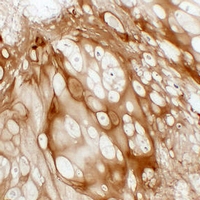

(Immunohistochemical analysis of Collagen 2 alpha 1 staining in human cartilage formalin fixed paraffin embedded tissue section. The section was pre-treated using heat mediated antigen retrieval with sodium citrate buffer (pH 6.0). The section was then incubated with the antibody at room temperature and detected using an HRP conjugated compact polymer system. DAB was used as the chromogen. The section was then counterstained with haematoxylin and mounted with DPX.)